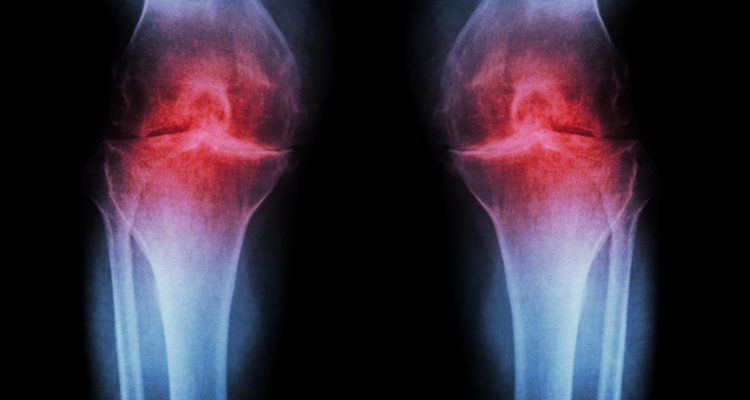

Артроз, или остеоартрит, – это дегенеративное заболевание суставов, которое поражает миллионы людей по всему миру. Оно характеризуется разрушением хрящевой ткани, покрывающей концы костей в суставах, что приводит к боли, скованности и ограничению подвижности. Понимание причин артроза и его связи с другими состояниями, такими как повышенное артериальное давление, является ключом к его профилактике и эффективному управлению. В этой статье мы подробно рассмотрим пять основных причин артроза и углубимся в то, как повышенное давление может негативно сказываться на здоровье ваших суставов.

- Естественный износ суставов: Даже при отсутствии травм или других предрасполагающих факторов, с течением лет хрящевая ткань может истончаться и терять свои свойства. Это одна из наиболее распространенных причин артроза, особенно в суставах, которые несут большую нагрузку, таких как колени и тазобедренные суставы.